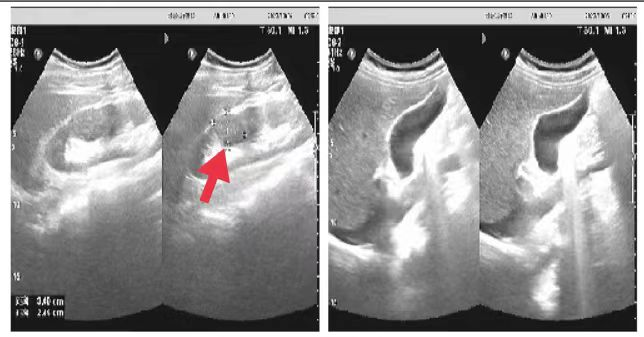

06、**男士,53岁

于2023年10月5日在邯郸仁泰南区体检,腹部彩超检查提示:右肾实质内见大小约3.0*2.4cm低回声,边界清,形态规整。诊断右肾低回声,建议客户到三甲医院进一步检查。首次回访:2023年10月10日电话回访,客户已在中心医院进一步检查, 明确病变的性质。2023年10月31日跟踪回访,客户已在中心医院完成手术治疗。